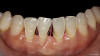

Patient "Cody" presented after having been referred by another dentist. The original dentist had worked patient up for veneers, but decided they were not going to work because there was severe recession and attachment loss, and veneer margins would be on root tissue next to recessed tissues, potentially causing bondability problems. The patient had good enamel (Figure 2), which practitioners did not want to cut. However, the patient did not like the coloration of his teeth.

This practitioner discussed pink and white composites with patient, suggested whitening, and mocked up pink composite around the roots and took photos. Although Cody's case was an advanced one, this was the first such case this practitioner was going to attempt with pink composite and new technique, and the technology was new as well. The patient was pleased with the esthetics and wanted to proceed.

From teeth Nos. 22 to 27, the patient had Miller Class III defects. He also had some recession spots, other areas that were Miller Class I and Class II, and old crowns that needed correction.